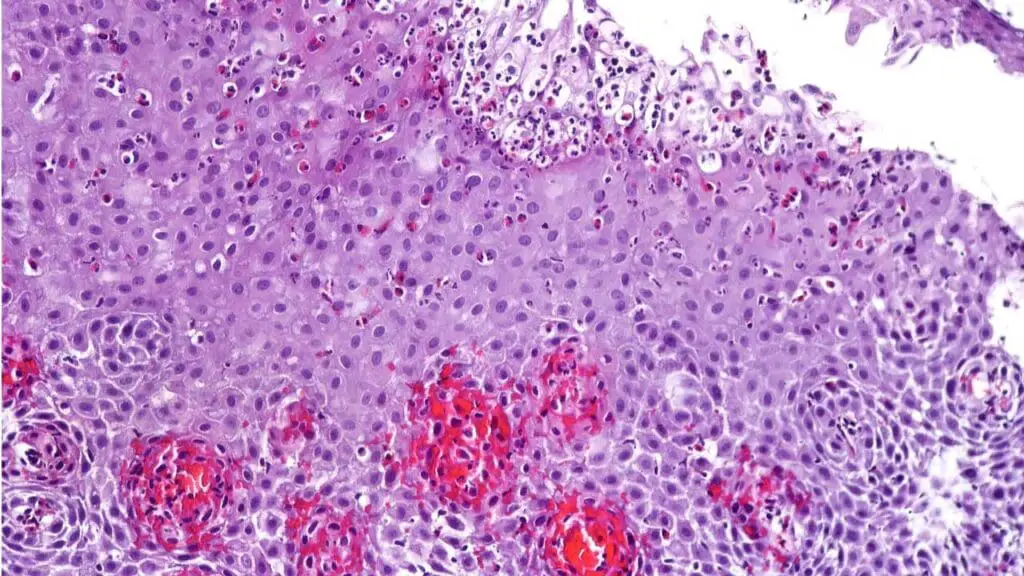

Eosinophils are a type of white blood cell, specifically a granulocyte, that plays a role in the immune system. They are characterized by their cytoplasmic granules that stain bright pink or red with eosin dye under a microscope. Eosinophils are particularly known for their involvement in defending against parasitic infections and mediating allergic reactions.